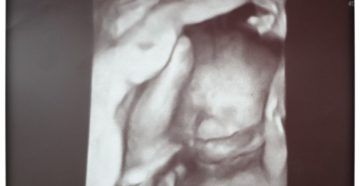

32 неделя беременности: рост, вес, развитие плода, УЗИ 32 акушерская неделя — является 30 неделей…

Обвитие пуповиной на 32 неделе беременности Обвитие пуповиной для большинства беременных звучит как страшный приговор….